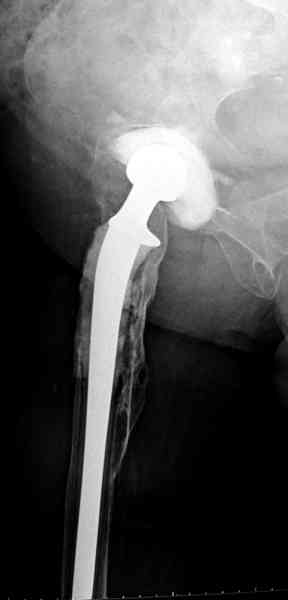

Приглашенный хирург установил ревизионный вариант бедренного компонента без замены ацетабулярного компонента, что осложнилось нагноением и свищами на уровне сустава и средней трети бедра. После двухгодичного безуспешного лечения перевязками и антибиотиками больная обратилась к нам на консультацию.

Для спейсера в бедро использовал старый длинный бедренний компонент меньшего диаметра, облепленный со всех сторон цементом с антибиотиком.

№3-6 снимки с осложнением

и последние снимки.